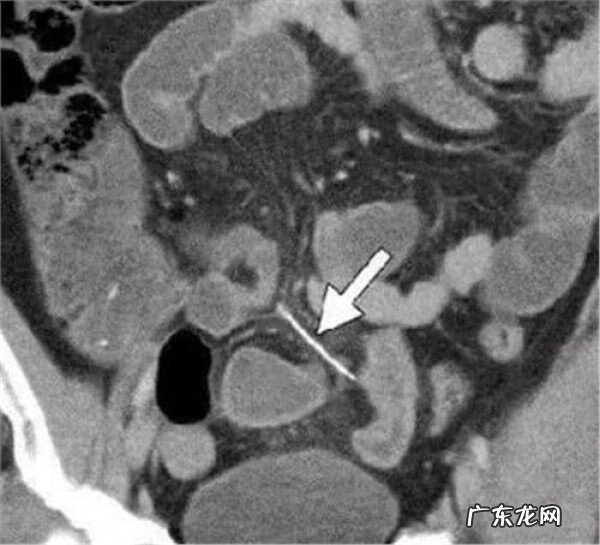

鱼刺扎破脖子

鱼刺刺穿肠道少数患者在异物取出后仍感刺痛不适,此时应告之医生,以便再次仔细检查是否还有其他异物存在,如果通过食道吞钡等方法反复检查,确未发现其他异物,可以服抗炎、镇静保守观察,一般不适感会逐渐消失 。每年因为鱼刺闹出的悲剧数不胜数 。尤其对孩子,一定要注意到鱼刺的危险性!